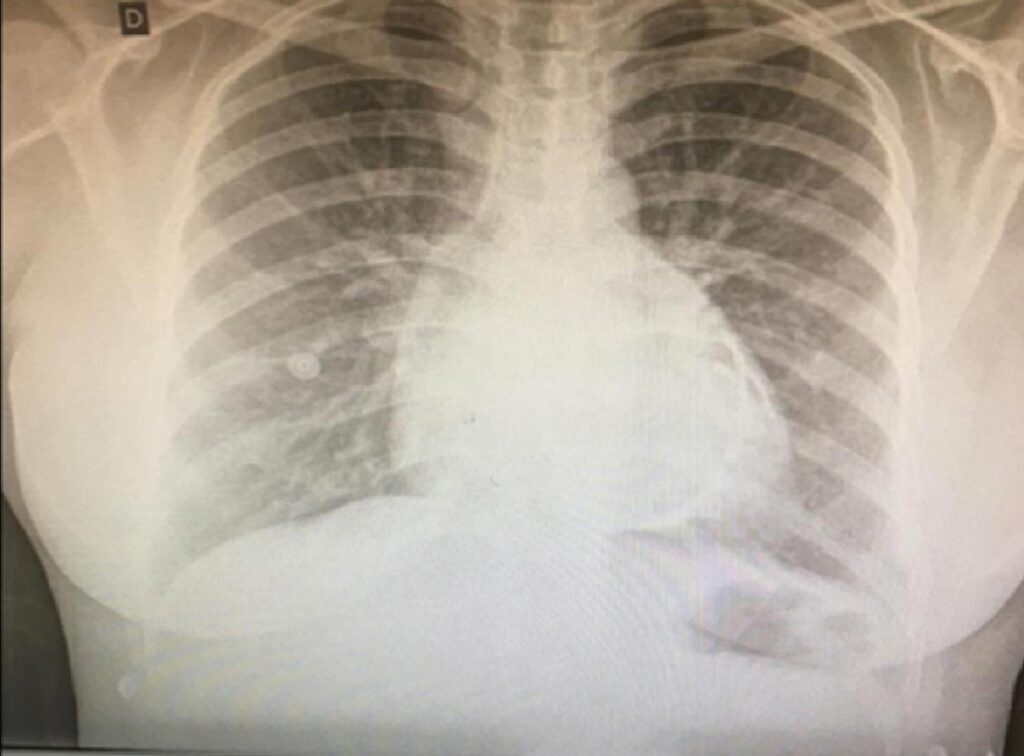

A Pericardite Constritiva (PC) é um diagnóstico diferencial desafiador de dor torácica na emergência cardiológica. Relatamos o caso de uma paciente que apresentava dor torácica há 7 dias, paa quem foi aventada a possibilidade de pericardite calcificada pela alteração da radiografia de tórax. Após ser encaminhada para serviço especializado de cardiologia, foi possível definir, por meio do Ecocardiograma Transtorácico (ECOTT) e da Ressonância Magnética Cardíaca (RMC), que se tratava de caso compatível com PC e havia necessidade de abordagem cirúrgica. Iniciado pela radiografia de tórax até a RMC. Os exames de imagem se mostraram cruciais para a suspeita, a confirmação e a definição do tratamento.